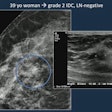

- Mammography vs. Ultrasound for Breast Tissue Analysis Mammography screening is one of the most recognized options for analyzing breast tissue in adult women. In contrast, the accuracy of this procedure allows it to be an alternative for women who cannot undergo mammography […]

- Contrast enhanced digital mammography anddigital breast tomosynthesis in early diagnosis of breast lesion

- The Role of Extended field-of-view Sonography and compound imaging in Evaluation of Breast Lesions

- Evaluation of breast masses on sono-mammography and colour Doppler imaging

- The role of sonoelastography in characterization of breast lesions

- Role of ultrasound elastography in the differential diagnosis of breast lesions

- Role of sonoelastography in assessing the response to neoadjuvant chemotherapy in patients with locally advanced breast cancer.